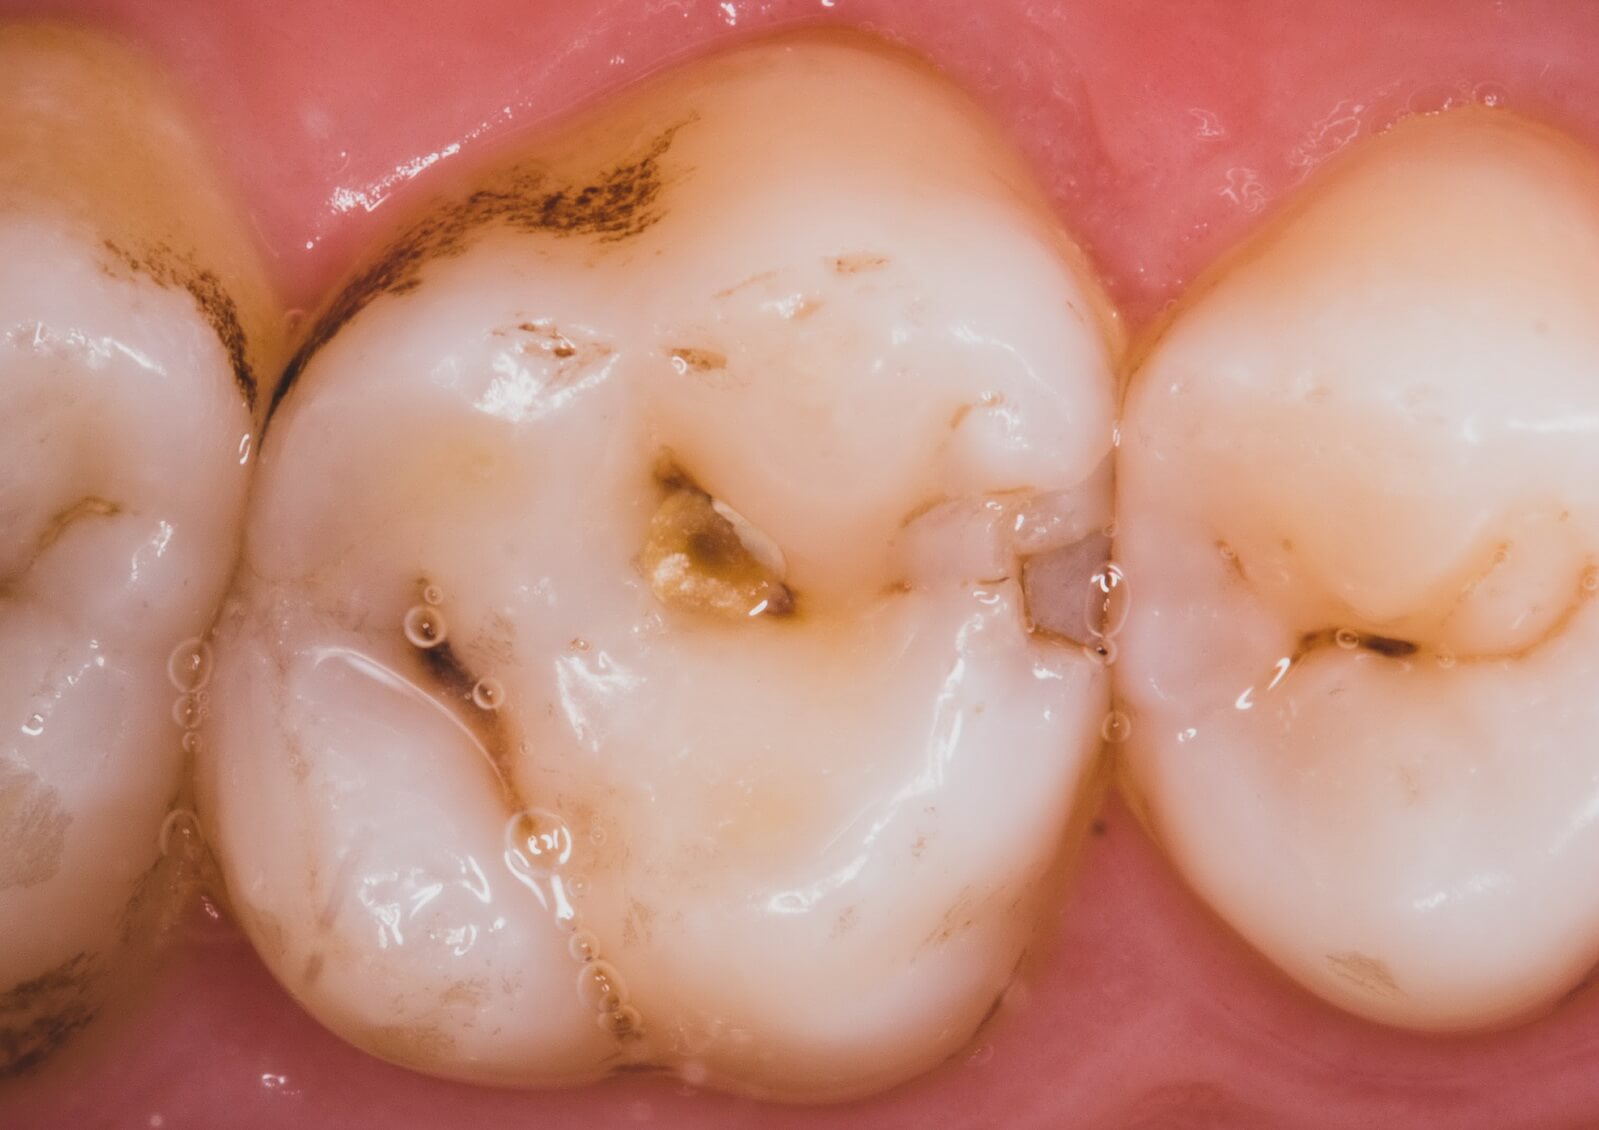

| Так в следующем клиническом случае (рис. 6) мы наблюдаем глубокую кариозную полость, сообщающуюся с полость зуба (осложненный кариес). | ![]() Рис. 6. До лечения. |

![]() Рис. 7. Отпрепарированные кариозные полости | После аккуратного препарирования под микроскопом нам удалось убрать кариозный дентин в основных полостях, при этом максимально сохранить объем своих твердых тканей зуба (рис. 7). |